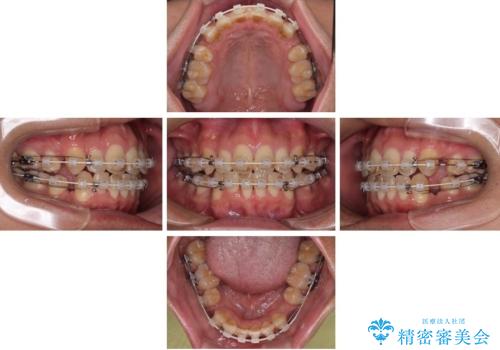

使用した装置は、透明感のあるプラスチックブラケットと白くコーティングされたワイヤー。

金属の装置に比べて目立ちにくく、治療中も自然な見た目を保ちながら矯正を行うことができました。

舌を前に押し出す癖(舌突出癖)があり、後戻りやオープンバイトの再発防止のため、MFT(口腔筋機能療法)も併用しています。